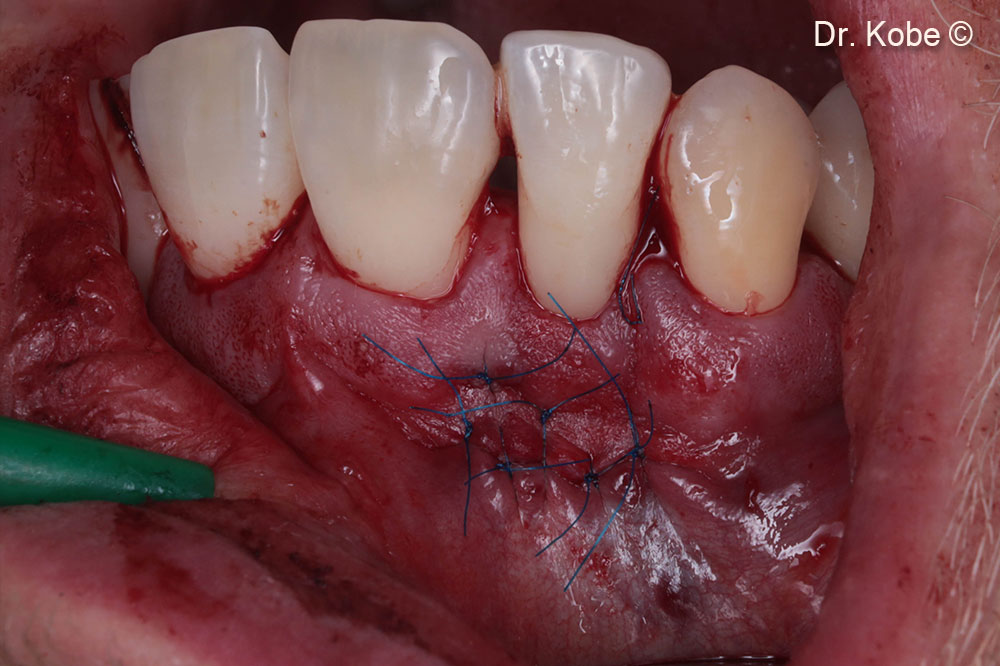

Wound sutured with interrupted sutures